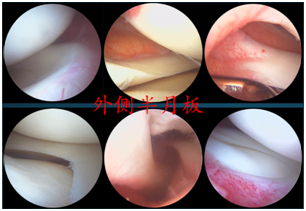

正常的半月板